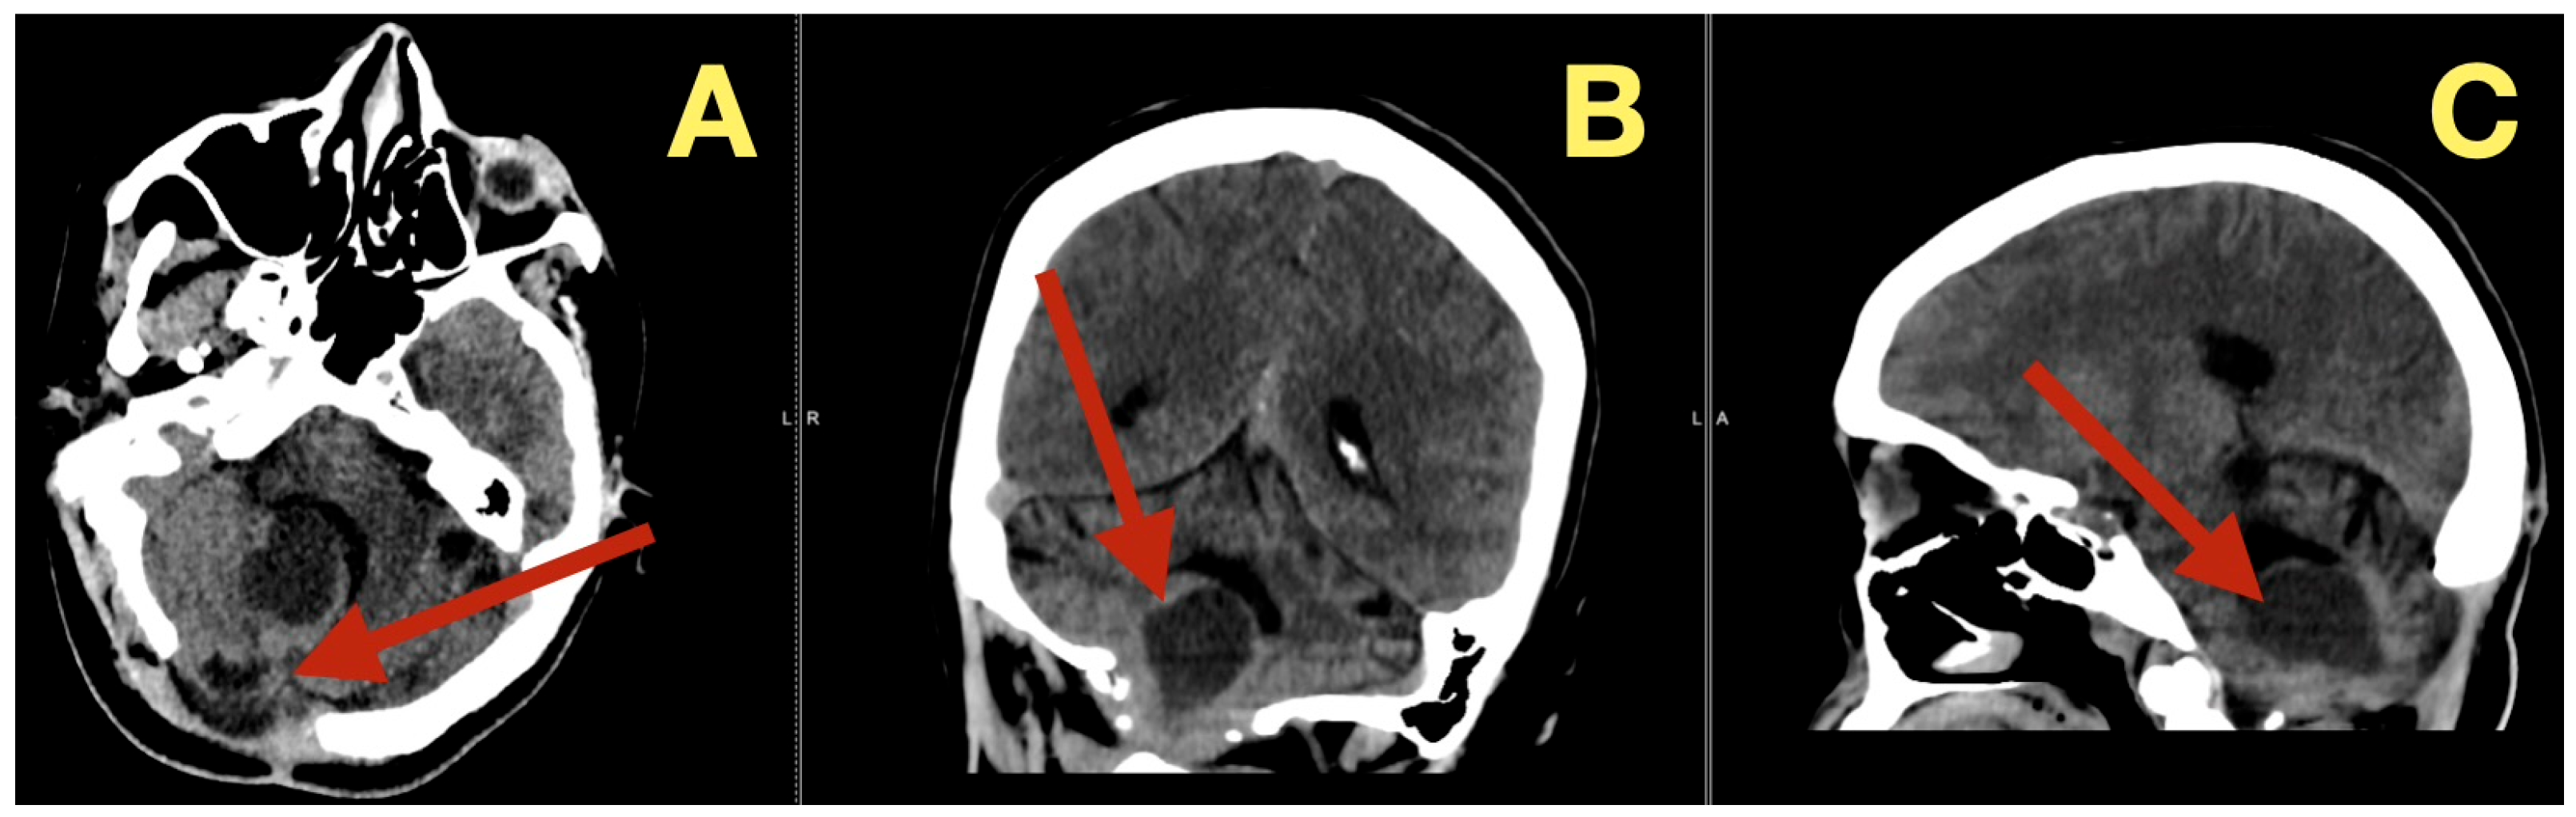

Follow up CT scans three months after surgery (Figure 6), confirmed continued decompression of the fourth ventricle and structural stability, as evidenced by stable size of the fourth ventricle, open CSF pathways, and absence of inflammation or scarring. The patient was clinically normal and able to resume all normal activities

Figure 6. Three-month postoperative CT scan. (A): Axial CT revealing sustained decompression of the fourth ventricle and preservation of the posterior-fossa configuration (arrow). (B): Coronal CT showing symmetrical cerebellar folia and patent lateral recesses without evidence of recurrent mass (arrow). (C): Sagittal CT confirming persistent brainstem relaxation, patent foramen of Magendie, and absence of postoperative scarring (arrow).